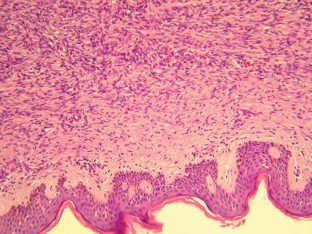

Dermatofibrosarcoma protuberans (DFSP) of the breast is a rare malignant tumor, and its preoperative diagnosis is extremely difficult. Local recurrence of DFSP is frequent after incomplete resection because of either false diagnosis or inadequate standard surgical excision. We present a case of DFSP that showed disconcordant results using different imaging modalities, suggesting that the MRI finding of subcutaneously located highly vascular tumor with suspicious kinetics but together with negative Cho peak on (1H) MRS, might be suggestive of the diagnosis of DFSP.